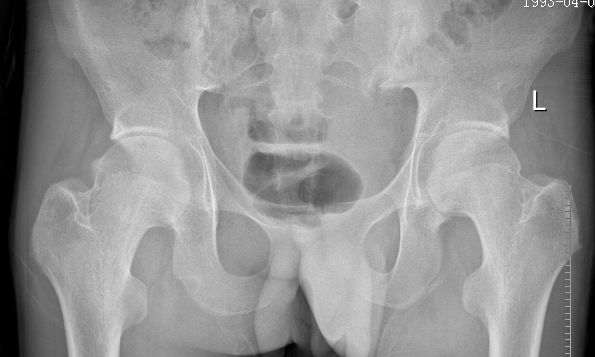

例1:21岁男性,AS患者,双髋关节疼痛伴活动受限4年

例1:行双髋关节置换后疼痛明显缓解,关节活动明显改善